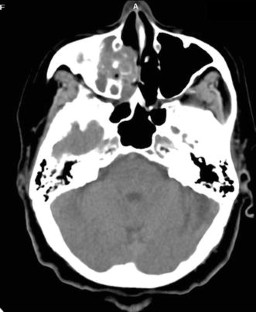

Though tuberculosis (TB) primarily affects lungs, extra pulmonary tuberculosis (EPTB) is also common, especially in high disease load areas and mainly manifests in ENT region. To study the different manifestations of tuberculosis in ENT region in terms of presentation, disease process, treatment and outcome. Records of patients diagnosed and treated for TB in the ENT region at our institute’s DOTS centre for a two and half year period were analysed for presenting complaints, examination findings, diagnostic features, treatment modes and outcome. Out of 3750 cases diagnosed as TB, 230 had EPTB. 211 cases had ENT manifestations. Majority of the cases were male and in the fourth decade of life. Commonest manifestation was cervical lymphadenopathy with 201 cases. Fine needle aspiration cytology was mostly diagnostic and category I anti TB treatment (AKT) achieved cure. The six cases of TB otitis media presented with ear discharge, sometimes bloody and had varied tympanic membrane findings and facial palsy in two cases with different types and degrees of hearing loss. Diagnosis was confirmed by histology of tissue removed during surgery. Patients completed category I AKT. Hearing and facial palsy did not improve. There were three cases of TB laryngitis and one of nasal TB both of which were confirmed by tissue diagnosis and responded well to AKT. Most of the results in the present study conform to findings of other studies. High degree of suspicion is necessary to reach diagnosis. Category I AKT is effective. Some cases may require surgery.

Fig. 2